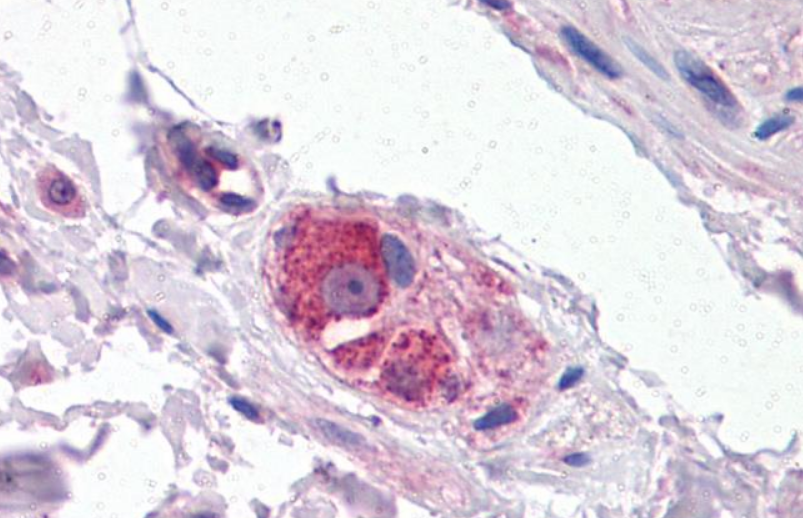

RARB Rabbit Polyclonal Antibody [orb11327]

FC, ICC, IF, IHC-Fr, IHC-P, WB

Bovine, Canine, Gallus, Porcine, Rat

Human, Mouse

Rabbit

Polyclonal

Unconjugated

50 μl, 100 μl, 200 μlTIG2 Rabbit Polyclonal Antibody [orb11481]